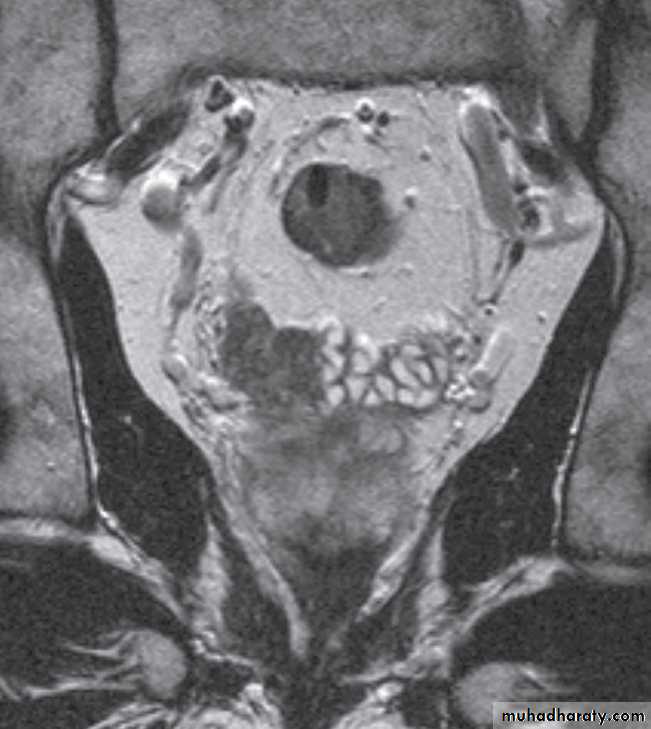

Magnetic resonance imaging is best imaging modality for staging , used to assess early stage prostate cancer in patients being considered for radical surgery or radiotherapy. Tumour in the peripheral zone is seen as a relatively low signal mass within the normal high signal of the peripheral zone on T2-weighted images.

MRI is used to demonstrate extracapsular tumour spread, to show invasion of the seminal vesicles, and to demonstrate possible lymph

node metastases .